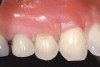

The 2-month postoperative view can be seen in Figure 13 through 15. Note the color match of the tissue, balance of the facial heights of contour, and zones of attached keratinized tissue present.

Figure 14  Case One The 2-month postoperative view, maxillary anterior.

Figure 14